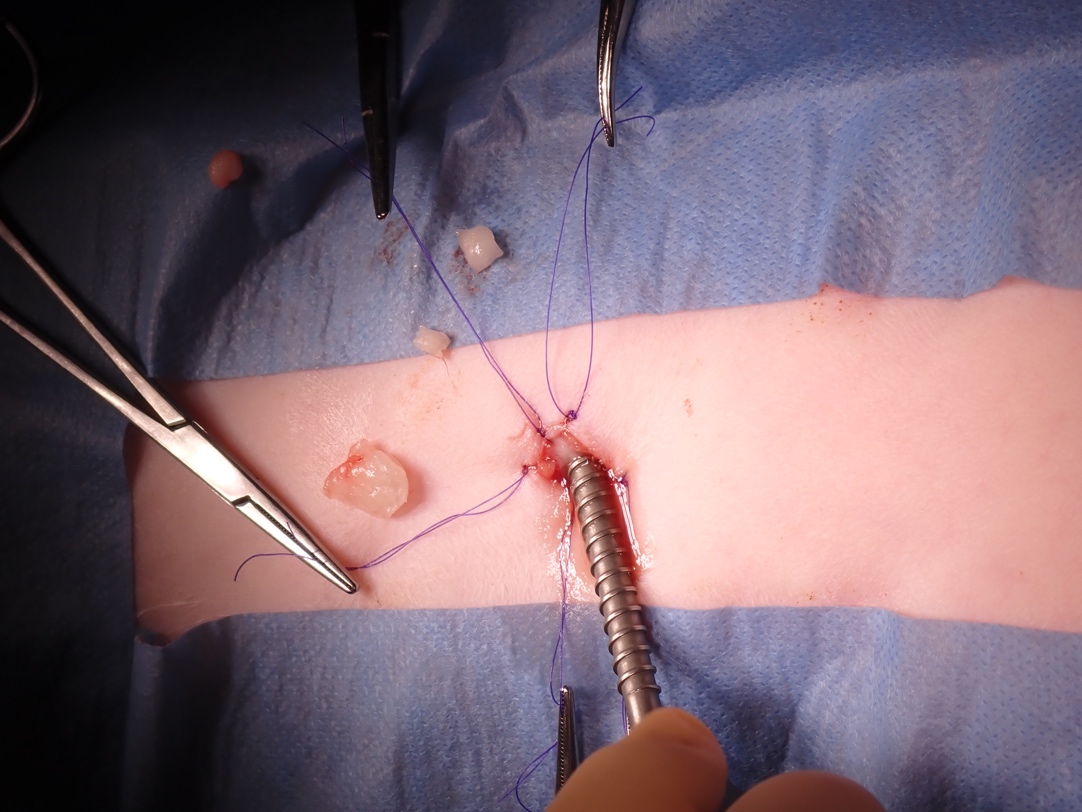

腹腔鏡でお腹の中を見ながら、膀胱の直上に小さな穴をあけて一度膀胱をお腹に縫合します。

膀胱に小さな穴をあけ、そこから3mmのカメラを挿入し膀胱内の結石を確認します。

膀胱内をカメラで観察しながら結石を鉗子でつかんでひとつずつ摘出します。